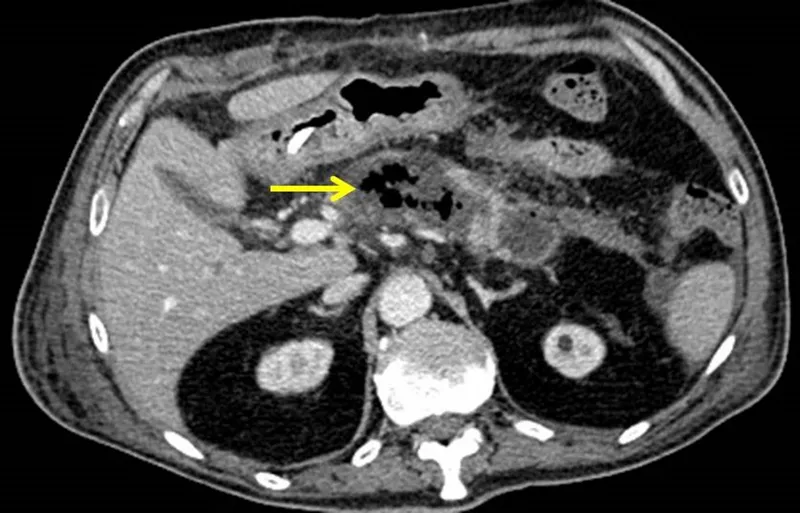

⭐ Infected necrosis is the primary driver of mortality. Gas bubbles on a CT scan are pathognomonic for infection by gas-forming organisms and mandate urgent intervention.